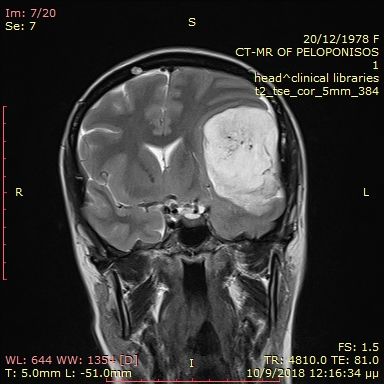

Preoperative large brain meningioma.

Postoperative MRI after total tumor removal.